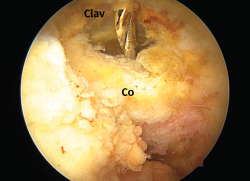

Figura 4. Los túneles óseos taladrados en el extremo distal de la clavícula (Clav) y el cuello de la coracoides (Co) se conectan entre sí mediante un hilo Vicryl® que hace de pasador final del dispositivo elegido. Hombro derecho con la óptica en un abordaje anterolateral.

La técnica artroscópica empleada fue la denominada de cerclaje de suspensión cortical coracoclavicular(2). Por encontrarnos más habituados, empleamos la posición de decúbito lateral y los portales de artroscopia posterior, anterolateral y 2 portales anteriores realizados para abordar el espacio subcoracoideo bajo visión directa, según la técnica descrita(5,6,7). En los 6 primeros casos empleamos el dispositivo AC TightRope® (Arthrex, Inc., Naples, Florida). A pesar de su analogía, pero motivado por el cambio de diseño realizado en dicho dispositivo y por el menor orificio requerido, en los 16 restantes casos hemos utilizado el dispositivo AC EndoButton TwinBrigde® (Smith & Nephew, London, England). En los casos con lesiones acompañantes, se emplearon los dispositivos OsteoRaptor 2,3® (Smith & Nephew, London, England) para la reconstrucción de las lesiones de tipo SLAP y el dispositivo TwinFix PK 5,5® (Smith & Nephew, London, England) para el tratamiento de las lesiones de los tendones del manguito rotador. En los últimos 6 casos hemos desestimado el empleo de las guías diseñadas para la implantación de estos dispositivos. Encontramos que su empleo es engorroso, dificulta la selección de los puntos de realización de los túneles óseos y prolonga el tiempo quirúrgico. Optamos por la inserción de las agujas-guía en el extremo clavicular al comienzo de la intervención (Figura 2). En este momento los relieves óseos son fácilmente apreciables. La selección del punto en el cuello de la coracoides se realiza de forma percutánea bajo visión directa (Figura 3). Tras realizar los túneles óseos por taladrado sobre las agujas-guía en la forma habitual, estos se conectan mediante un hilo Vicryl® n.º 2 (Ethicon Endo-Surgery Inc., Cincinnati, Ohio, United States) que hace de pasador final del dispositivo elegido (Figura 4). Si es necesario, se completa la reparación de la fascia trapeciodeltoidea y/o de la cápsula acromioclavicular superior a través del miniabordaje superior asociado.